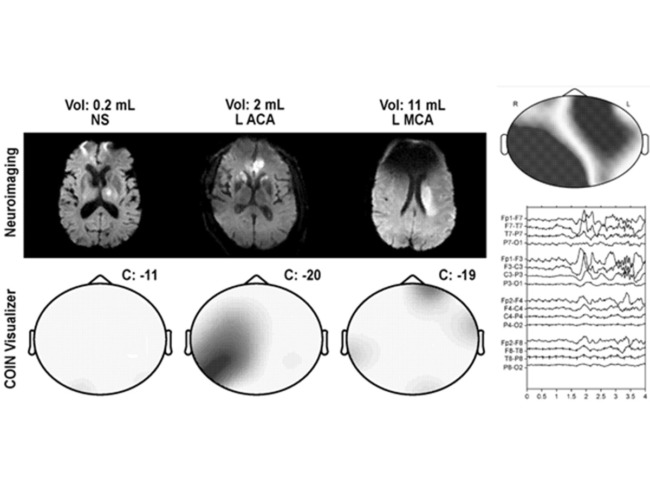

Patent: “Methods and systems for detecting stroke.”

Point-of-care brain monitoring algorithm for detecting stroke in children

In what represents their first patenting, a researcher from the University of California is seeking protection for non-invasive methods of brain monitoring that use electroencephalography (EEG) to detect new or worsening brain injury in pediatric patients. Read More